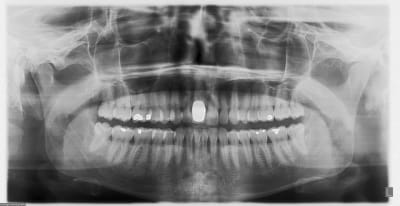

pluton

22/10/2011 à 09h57

joli drmarcus

moi non plus, vu le défaut osseux, je n'aurais pas fait de MCI

je parle bien de défaut, si c'est l'infection qui bouffe la corticale...mais si c'est toi qui l'enlève à la pince gouge, c'est différent...

perso, je préfère conserver la paroi osseuse, même si je ne me fais pas trop d'illusion sur sa persistance...au moins, elle me maintient mon biomat un certain temps...

chose qui a été faite dans ce cas...désolé j'ai perdu les photos de la chir, on ne voit que la phase prothétique

le biomat est du kasios tcp, on voit quelques granules qui s'éliminent de la gencive

une série de photo le jour de la pose, puis 15j après (prothèse réalisée par mon confrère)

Pano u7x6bm - Eugenol